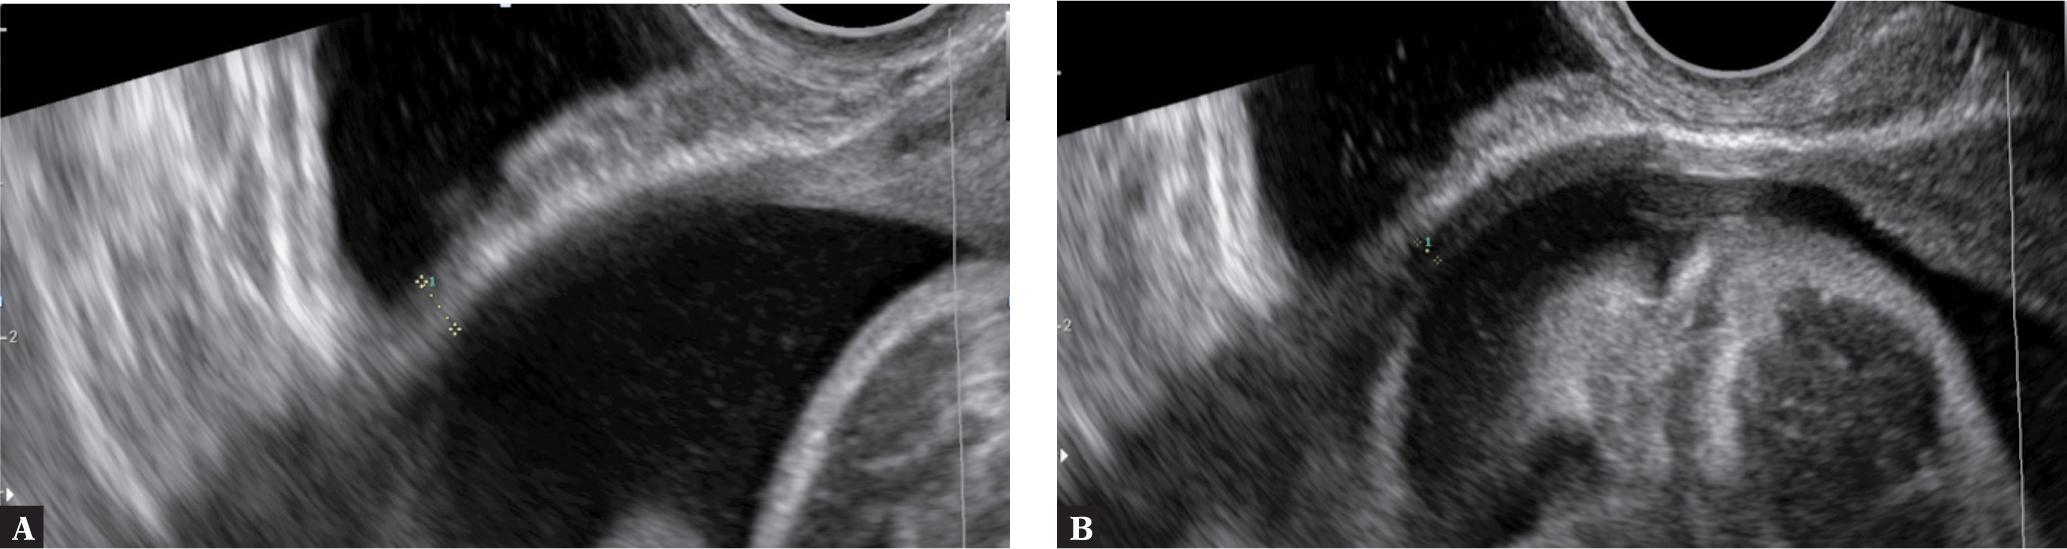

Jastrow et al., in turn, analyzed 20 studies assessing CS scar thickness by US, covering a total of 1834 women. A perinatal CS defect was found in 121 pregnant women (6.6%). The authors performed a statistical analysis of the results regarding the thickness of the lower uterine segment (LUS), defined as the smallest measurement between the amniotic fluid and urine in maternal bladder. They also analyzed the myometrial thickness, or the myometrial layer (ML), described as the smallest hypoechogenic portion of LUS (Fig. 2). The optimal cut-off value in the evaluation of the risk for CS scar rupture ranged from 2.0 to 3.5 mm for full LUS thickness, and from 1.4 to 2.0 mm for ML. The authors stressed in their conclusions that LUS may be considered a strong prognostic factor for a CS scar defect in women considering a vaginal birth after a cesarean section (VBAC)(13).

A. Measurement technique for LUS thickness. B. Measurement technique for ML thickness